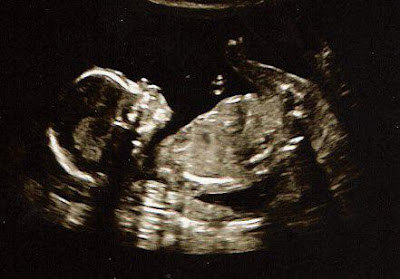

The latest ultrasounds…

Cool, huh? And the new ultrasound technology is wild…

man, those pics are getting gooooood

Awesome! Way cooler than the sono pics we have of ours. Congrats.